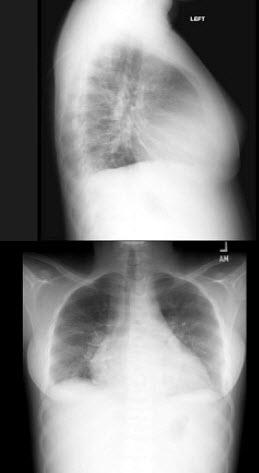

7、单项选择题

男,48岁,常感胸闷气逼,近1月渐加重,X线检查如图,最可能的诊断是()

A.右侧气胸

B.右侧肺大泡

C.两肺肺大泡

D.正常胸片

E.肺气肿